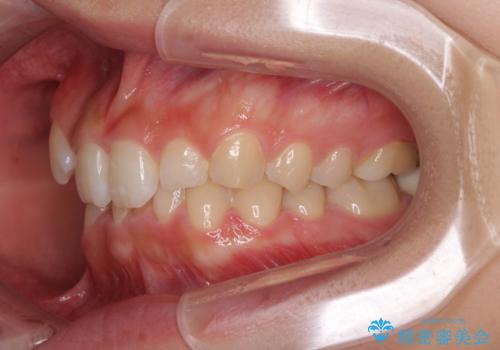

- 上顎の重なっている前歯を気にして来院された患者様です。

八重歯改善には抜歯が必要で、八重歯の移動量が多く、更には右側にずれている正中を改善する必要がありました。

インビザライン単体での治療は困難と判断し、補助装置により八重歯移動後にインビザラインを用いることとしました。

インビザラインでは治療期間が延びることが予想されたため、ワイヤー矯正を提案しましたが、セラミッククラウンが多く、壊すあるいは傷が付く可能性があることから、長期間であってもインビザラインを選択されました。